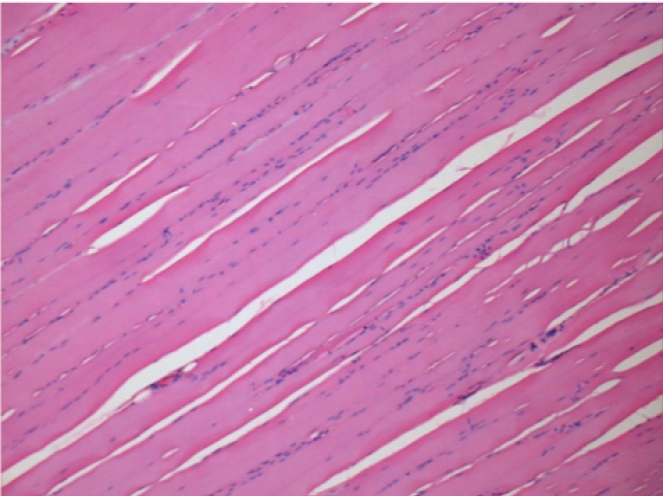

L:Pretibial-No treatment

10 days after Endopeel Injection 0.1ml in the right pretibial muscle.

Here you may see the formation of the vacuoles which are surrounded by lymphocytes. Vacuoles are different from tissue necrosis . The presence of lymphocytes is related to the permeability of the cell membranes.